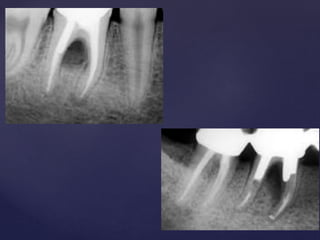

One should take care to avoid carrying all the Gates-Glidden drills

to same level which may lead to excessive cutting of the dentin,

weakening of the roots and thereby “Coke-Bottle Appearance” in

the radiographs.